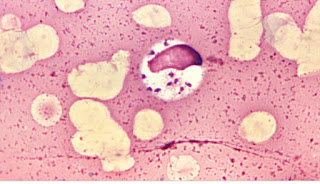

Leishmaniasis, one of the dangerous tropical and subtropical diseases which is caused by a flaggelated protozoa parasite known as leishmania, of the order Kinetoplastodia.The parasite, leishmania which is usually transmitted through the bites of infected female sandflies of genus Phlebotomus and Lutzomyia.The disease became known as Leishmaniasis after William Leishman in 1901 when he discovered an ovoid bodies in the spleen of one British soldier experiencing fever,anaemia and muscular atrophy.Leishman described this illness as “dum dum fever” and published his findings in 1903 It is estimated that there are 0.9 to 1.6 million new cases of leishmaniasis and 20,000 to 30,000 deaths annually.Many factors are known to facilitate the transmission of the disease: Poverty, resulting in poor housing and sanitation conditions (e.g. garbage and open sewers) which may increase insect breeding and resting sites and facilitate transmission to humans. Leishmaniasis is associated with migration and the movement of people to areas with existing transmission cycles.The disease can present in three clinical forms:

Visceral Leishmaniasis known as Black fever or Kala-azar is caused by the Protozoa parasites, Leshmania donovani and Leshmania infantum. Kala-azar is potentially fatal if left untreated.isceral leishmaniasis cases are usually recorded in poor, remote, and politically unstable areas where there is limited health care and patients have little access to affordable medications. Half of clinical cases of kala Azar occur in children and It is estimated that about 90% of the 50,000 to 90,000 new cases arising each year occurs in the rural areas of India, Sudan, South Sudan, Kenya, Somalia, Ethiopia, and Brazil, and that only 30% of cases are reported.